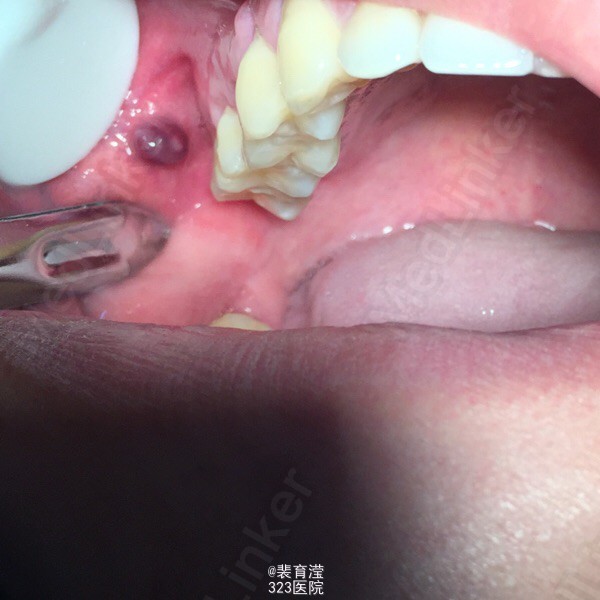

患者,男,23 主诉:右侧颊部异物不适数月 现病史:患者自述数月前右侧颊部出现异物不适感,现前来检查 要求治疗 既往体健 否认全身系统性疾病 药物过敏史及传染病史

检查:右侧上颌第一磨牙,颊部前庭沟底,直径1.5mm 囊肿,探不适,波动感。 右下第三磨牙 近中阻生